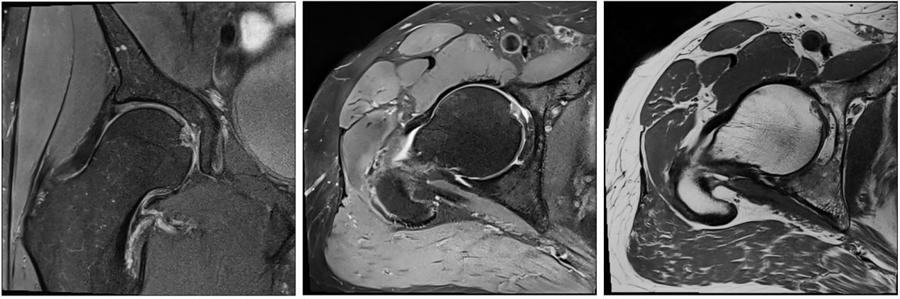

骨肌系统--UltraFlex Large 18 可以提供更高分辨率及更小FOV髋关节成像。